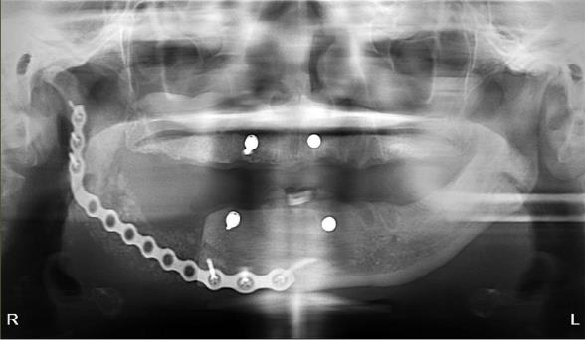

Case 3

The patient is a 76-year-old female with a history of multiple myeloma who was referred by her dentist for a full mouth extraction prior to starting Zolendronic acid (Zometa) infusions. Her past medical history was further complicated by cardiovascular and pulmonary issues, along with Type II diabetes and general frailty. After discussion with her dentist, the decision was made to switch from full mouth extractions to removal of symptomatic teeth. The patient underwent removal of teeth #20, #23, #24 and #27 in August 2023 and began her infusions three months later. The patient did well and returned for removal of teeth #21 and #22 in the spring of 2025. At that time, she had also been started on a combination of daratumumab (Darzalex), a monoclonal antibody, and bortezomib (Velacade), a proteasome inhibitor, for her multiple myeloma. After two months, the patient developed pain and bone exposure at the site of #21/#22. She also reported pain in teeth #5, #14 and #16. She was diagnosed with Stage 2 MRONJ. The area was debrided and teeth #5, #14 and #16 were removed. Currently, she is pain-free and there is no evidence of bone exposure or MRONJ.